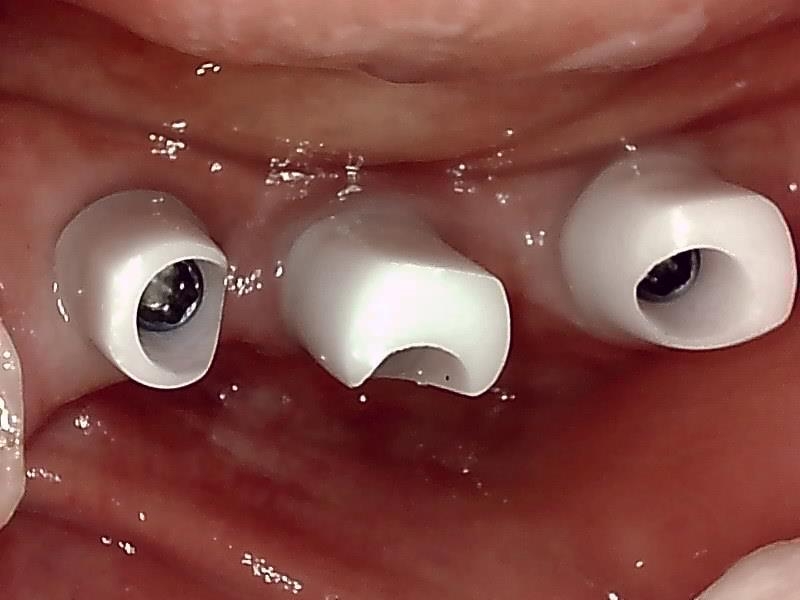

抜糸後、2週間経過した歯肉の状態です。

歯肉の整形 (左下)とても綺麗な良い歯肉の状態です。

アバットメント装着 (左下)

(ジルコニアアバットメント)